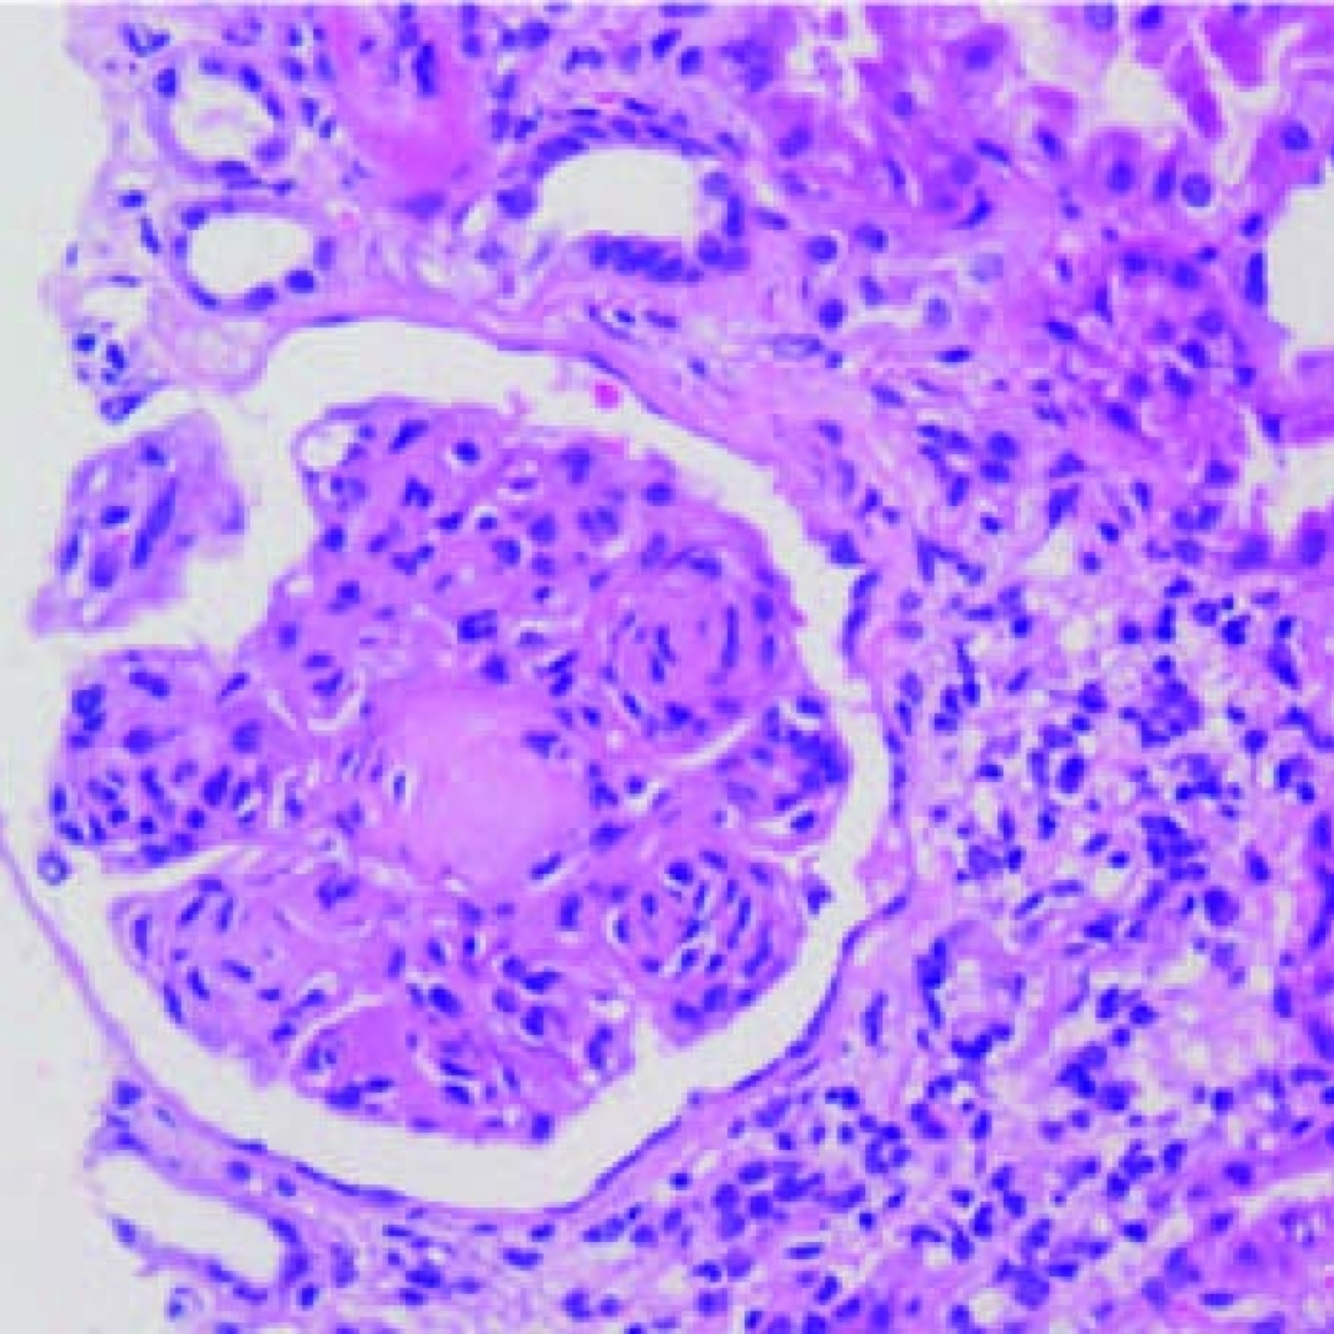

rapidly progressive glomerulonephritis : crescent moon shaped